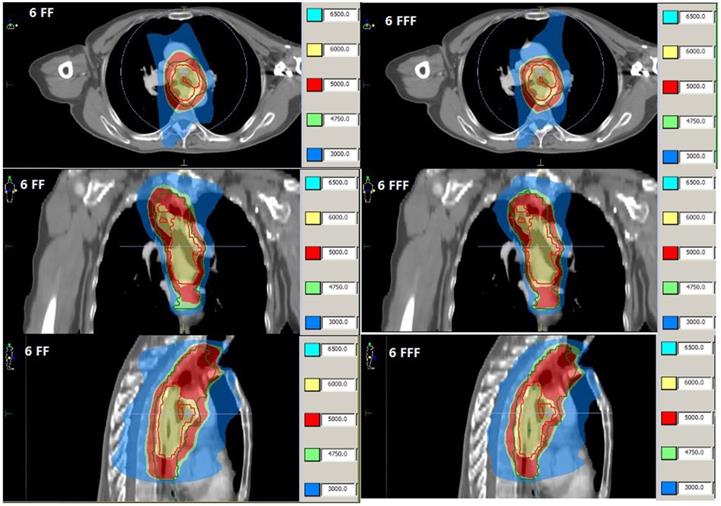

The averaged volumes of these randomized selected twenty eight patients were 184.4 cc (ranged from 53 cc to 502cc) for PTV1and 621.3 cc (ranged from 192.6cc to 975 cc) for PTV2, respectively. The target dose coverage were compared in Table 2, the results indicated there is no significant statistical discrepancy between 6FF and 6FFF in target dose coverage for plan comparison. The examples of representative dose distribution and DVHs for esophageal carcinoma cases are showed in Fig. 1 and Fig. 2.

Fig 1

Dose distributions from VMAT of patient 3 with FF beam (Left) and FFF beam (Right).

For esophagus carcinoma, the pulmonary toxicity is a serious possible side-effect of treatment. So the dose constrain to bilateral lung is priority to consider for evaluation of treatment plans. Numerous literatures had been published with conflicting parameters for prediction of pulmonary toxicity [13,14], but it was still quite difficult to make comparison between studies. In this study, the V10Gy, V20Gy and V30Gy were used for evaluation of pulmonary toxicity. Mary V.G stated when the total lung V20Gy is <25%, the very low risk of pneumonitis would occur [15]. For these two contrast plan groups with FF beams and FFF beams, the average values of V20Gy and V30Gy are both very close, meanwhile, the V20Gy is less than 30% and V30Gy is less than 20%, they are all within dose constrain tolerance and no significant statistic difference for both plans. But this isn't indicating that there isn't a significant difference in special case such showed in Fig. 1.